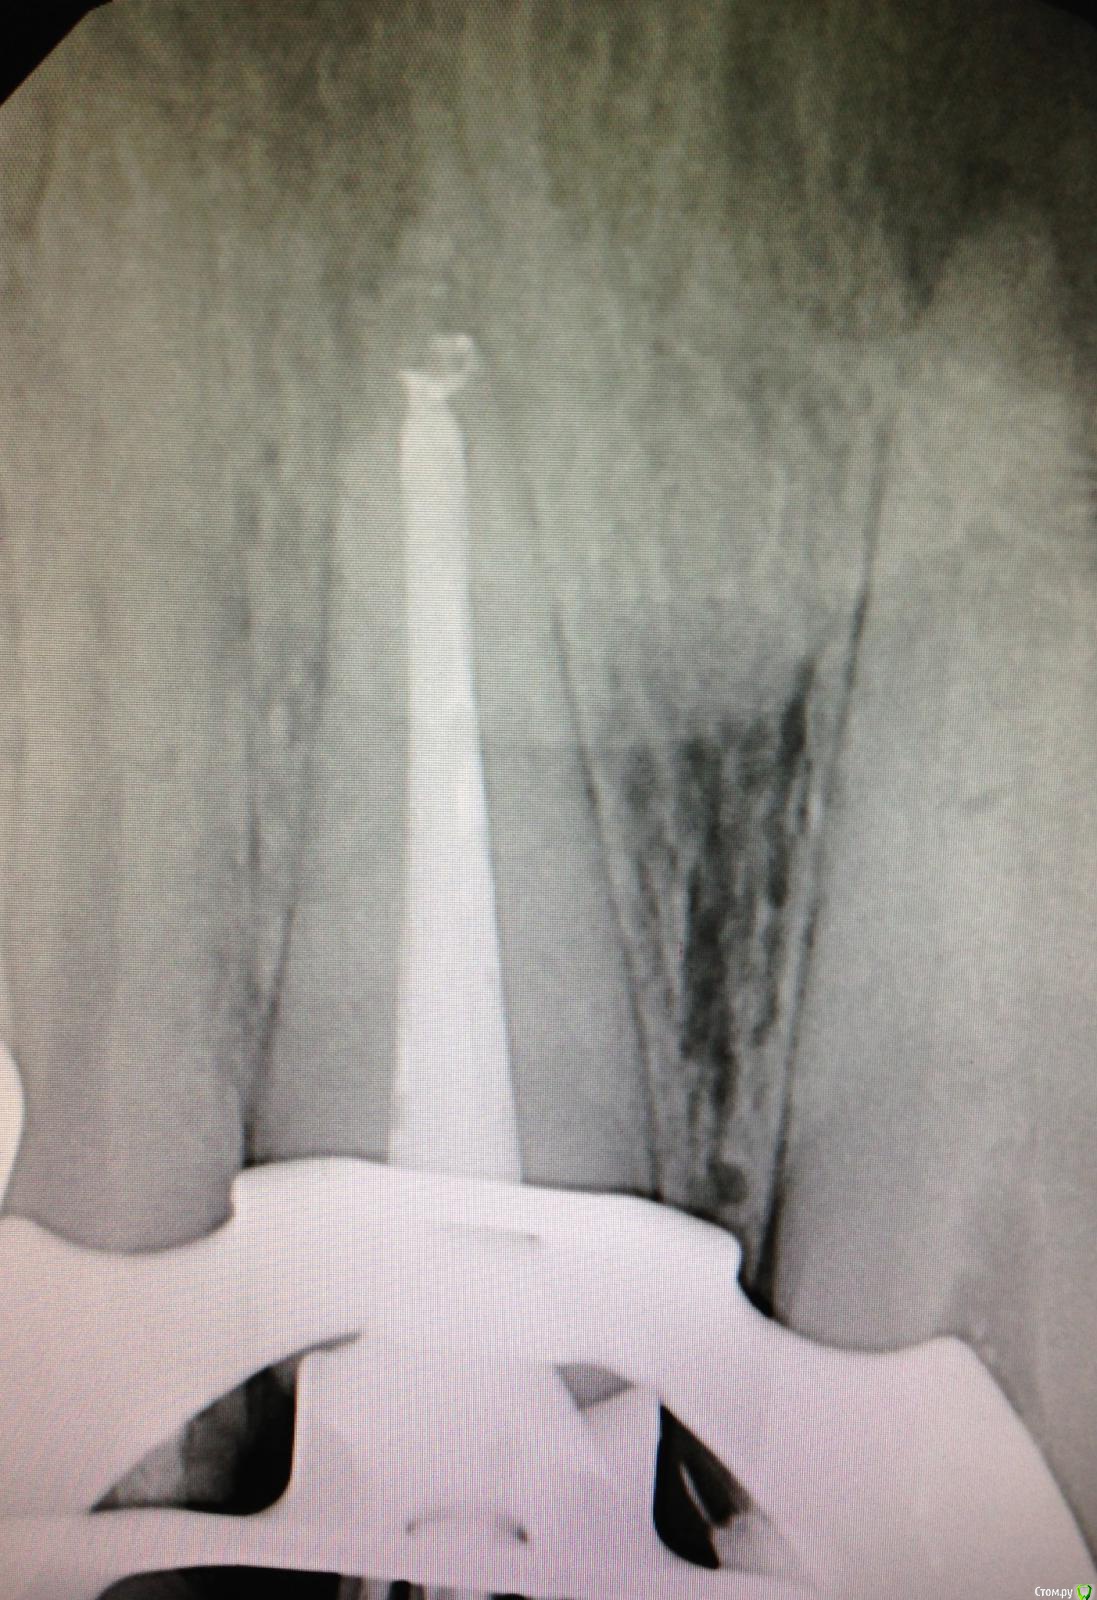

Natalia :) Опубликовано 16 декабря, 2014 Поделиться Опубликовано 16 декабря, 2014 Так. Только стоило отвлечься- понакидали снимков своих. НегодяиСорри,я парочку выложу,потому что мне срочно нужно понять,что я не так делаю...Принимаю самую жесткую критику,потому что и сама все вижу,сравнивая свои с вашими красивыми картинками)работаю первый год,но хочется,конечно, сразу хорошо работать...Про спредеры и гутту поняла,завтра буду выполнять рекомендацию,спасибо)На этом снимке не понимаю,что за хрень нечеткая по стенкам к.к?и тут хрень какая-то пористая,еще и в апикальной трети(здесь полость раскрыта ужасно,знаю,плохой обзор был.Спасибо за внимание 3 Ссылка на комментарий